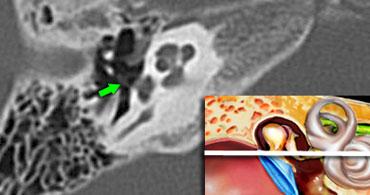

Một lát cắt coronal hơi ra phía sau hơn sẽ cho thấy dây thần kinh mặt hai lần.

Phần phía trong là đoạn thoát ra khỏi ống tai trong và chạy về phía hạch gối (mũi tên trắng phía trong).

Phần phía ngoài là đoạn chạy theo hướng ra sau, xuất phát từ vòng chữ U của gối thứ nhất.